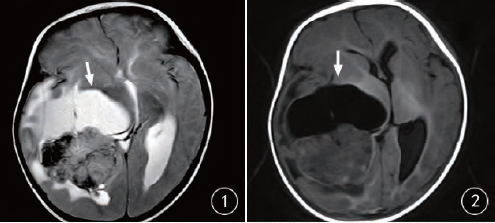

摘要:橫紋肌樣瘤最新治療技術(shù)為小巷深處的生命之光,帶來(lái)了新的希望。通過(guò)采用最新的治療技術(shù)和方法,醫生們能夠更有效地應對橫紋肌樣瘤,提高患者的生存率和生活質(zhì)量。這些新技術(shù)包括先進(jìn)的手術(shù)方法、藥物治療和放射治療等,為患者提供了更多的治療選擇和更好的治療效果。

橫紋肌樣瘤是一種罕見(jiàn)的腫瘤,但生命綠洲卻憑借其獨特的醫療視角和先進(jìn)的設備,走在治療的前沿,這里采用的治療技術(shù)不僅結合了傳統手術(shù)的優(yōu)勢,還融入了最新的生物技術(shù)、基因療法和免疫治療等前沿科技,經(jīng)驗豐富的醫療團隊緊跟國際醫學(xué)的最新進(jìn)展,不斷嘗試將最新的研究成果應用到臨床實(shí)踐中。